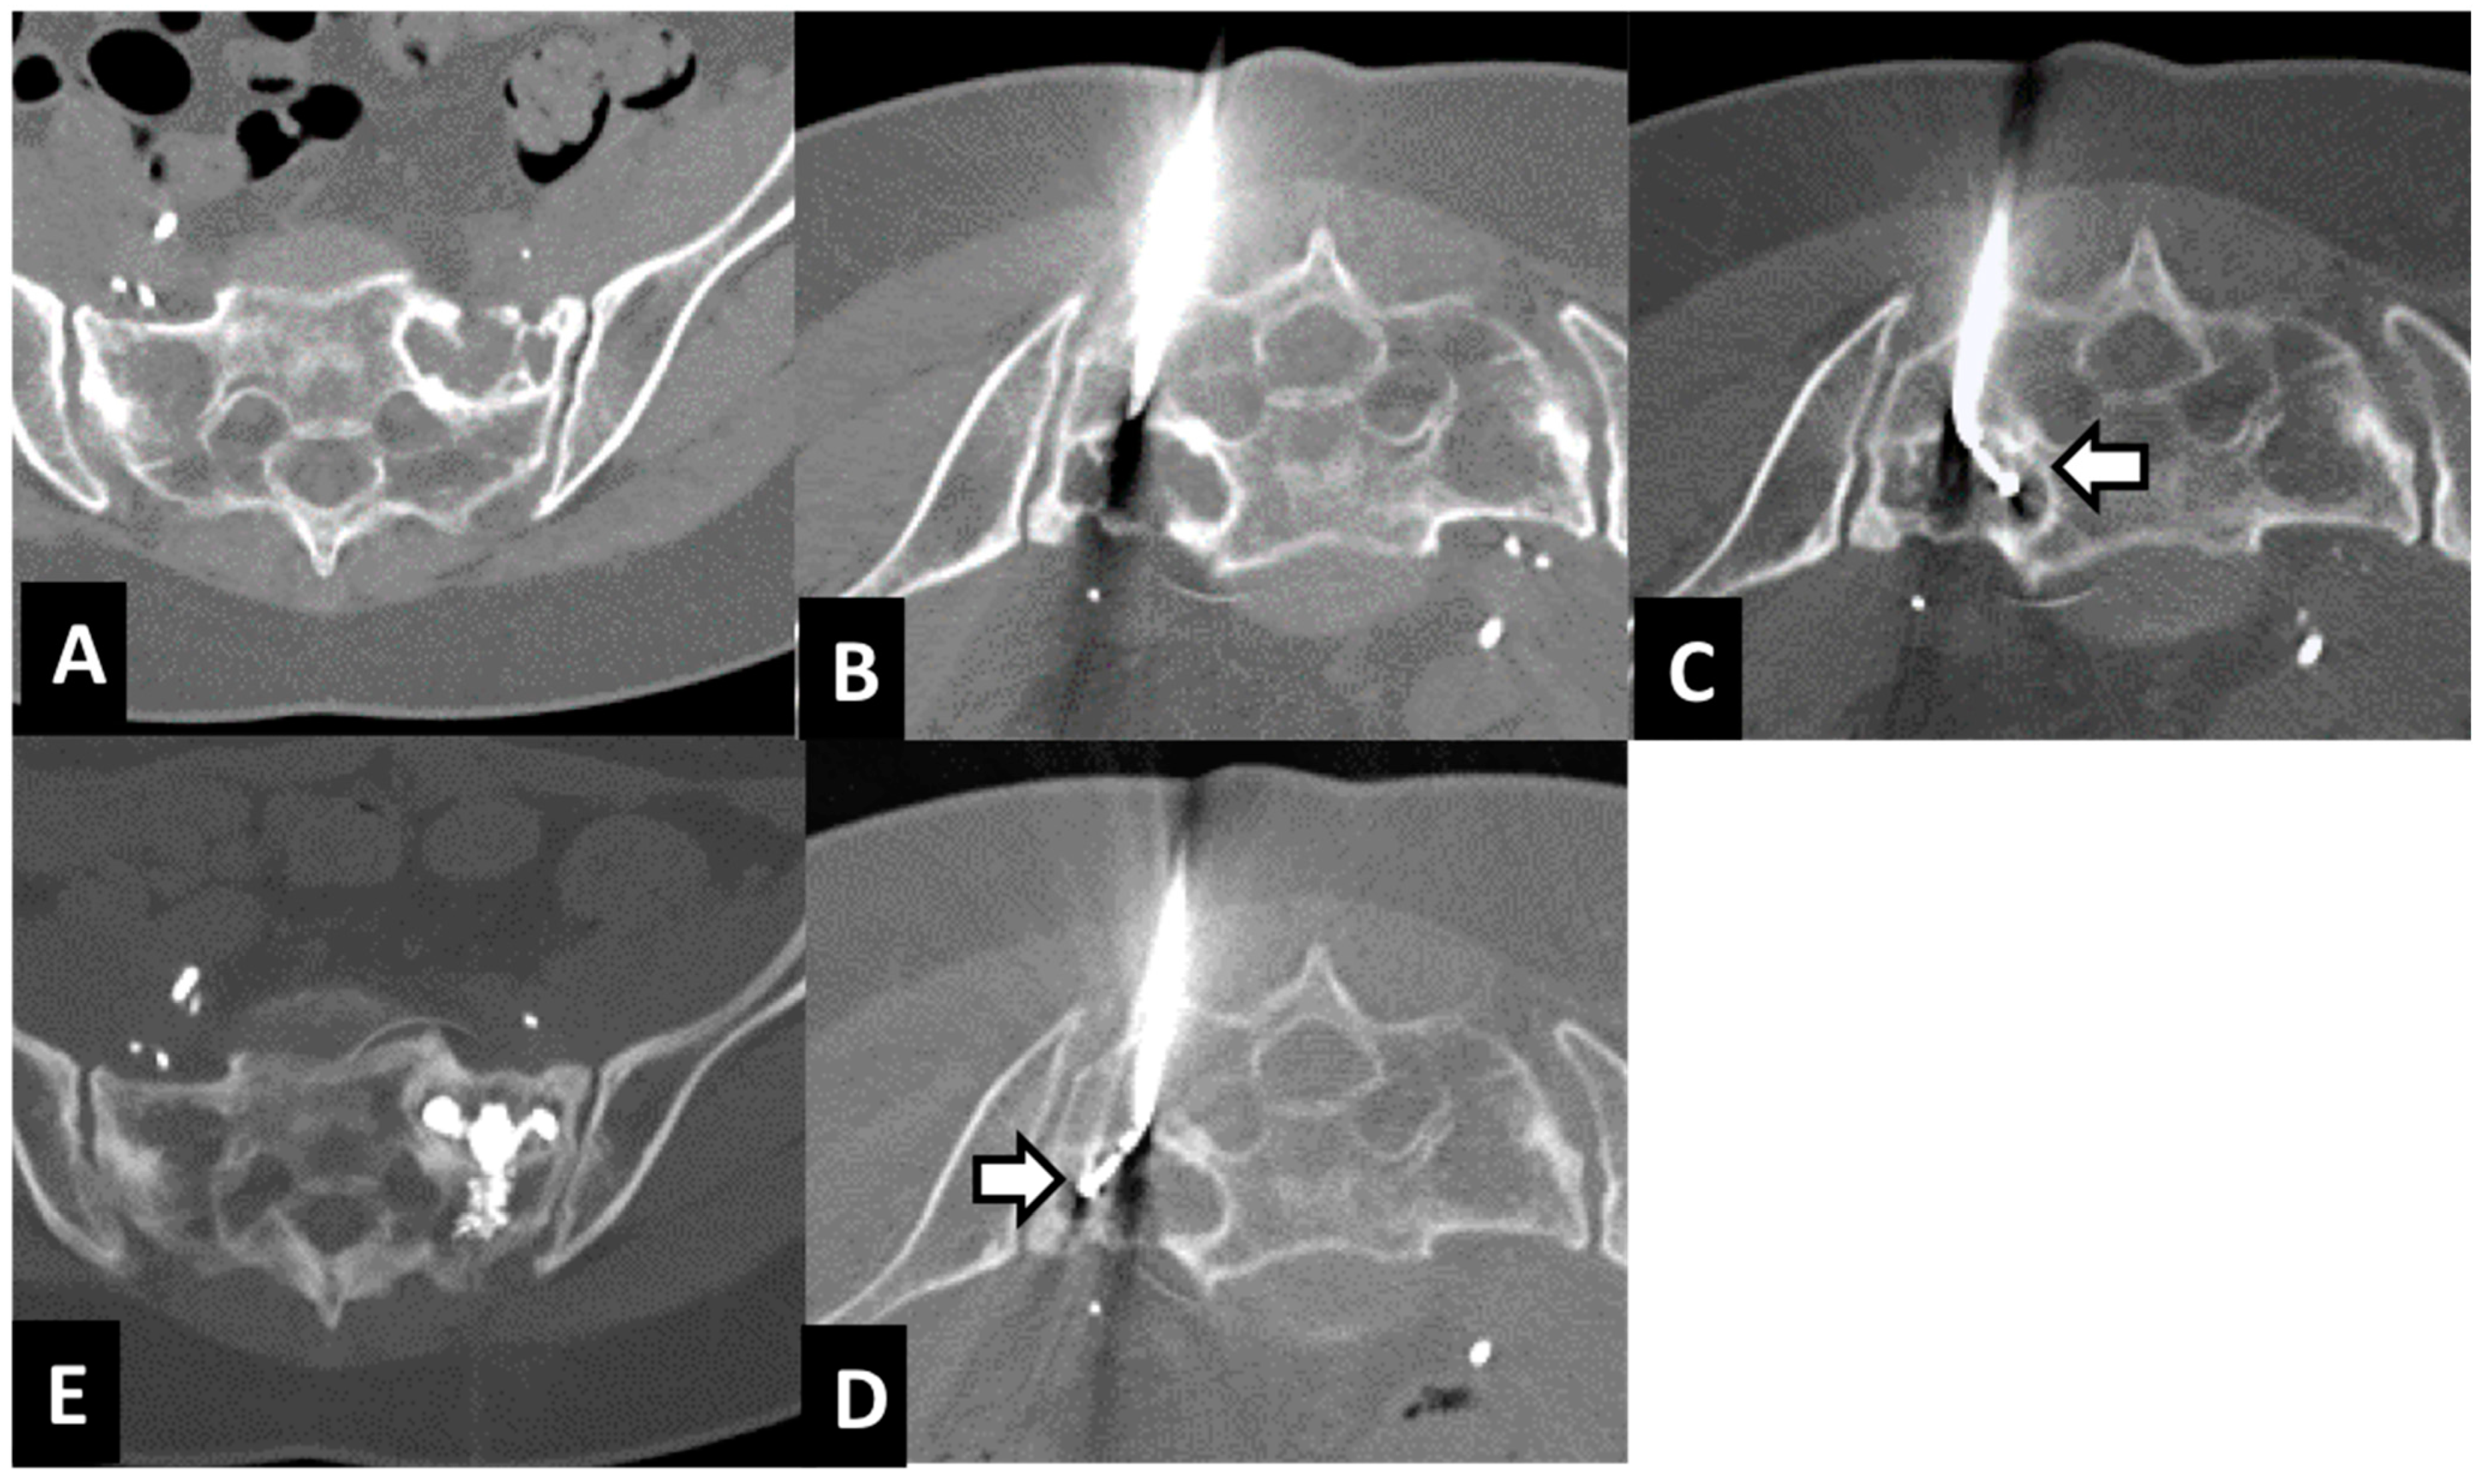

2.2. Radiofrequency Ablation (RFA) and Cementoplasty Procedure

| 69—M | Renal cell carcinoma | sacrum | 30 × 32 × 28 mm | 2 1 | 7 | 3 1 0 0 0 | 4 cc | none | CT |